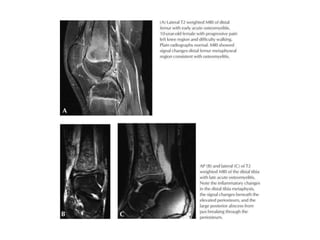

Femur AP

Femur LAT

LEG AP

LEG LAT